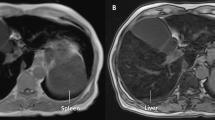

Three cases are reported in this study; in each case, HFE genotyping was negative, and liver specialist assessment was undertaken. Case 1 was a 62-year-old male who over the past 7 years had raised serum ferritin (SF) ranging between 1261 and 1675 μg/L (normal range 30–300 μg/L), with transferrin saturation (TS) 40 to 53% (normal range 20–55%). His alanine aminotransferase (ALT), aspartate aminotransferase (AST), and gamma-glutamyl transferase (GGT) levels all remained normal during this time. Liver biopsy revealed grade 4 stainable iron in hepatocytes, with accentuation of iron in the pericanalicular region (Fig. 1). No other pathology was noted. In case 2, a male aged 51 who did not consume any alcohol, presented with a SF of 1714 μg/L and TS of 34%. ALT, AST, and GGT were all normal although ultrasound revealed a diffusely echogenic liver suggesting fatty liver. Ferriscan identified a hepatic iron concentration of 44 μmol/g (normal range 3–33 μmol/g). In case 3, also male aged 62 presented with a SF of 1133 μg/L and TS of 90%. His ALT, AST, and GGT levels were mildly elevated. Liver biopsy demonstrated grade 1 iron with a hepatic iron content of 39 μmol/g and F1 fibrosis. Case 3’s pathophysiology is complex with positivity for α-thalassemia trait and hepatitis C virus (genotype 2).